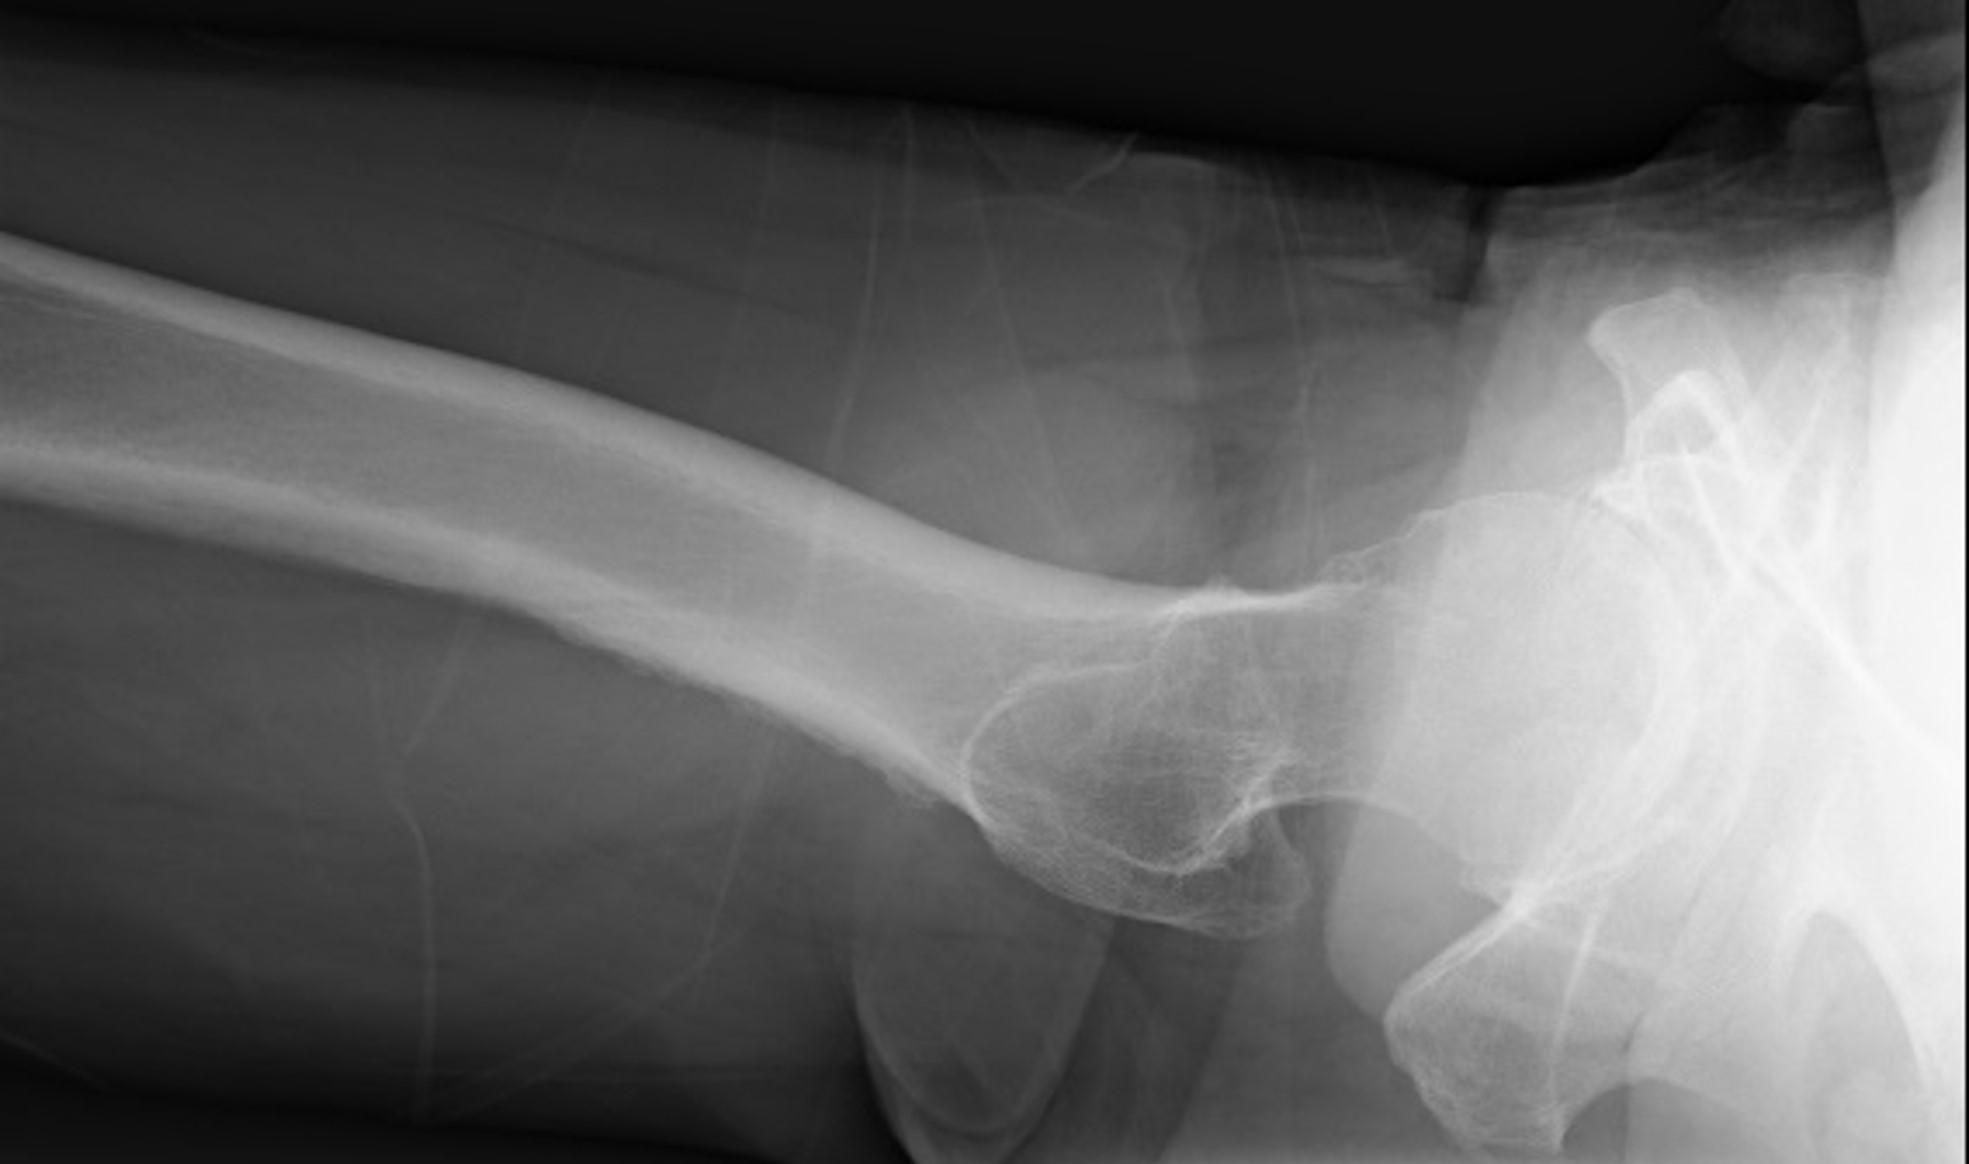

70歳代男性、検査前日に転倒しその後から右股関節痛があり歩行不能となった。図3、4にX線単純撮影を示すが、骨折を認めなかったためDE撮影を行った。

RevolutionApexElite_Uonuma204.jpg図3 両股関節 正面像

図4 右股関節 軸位像